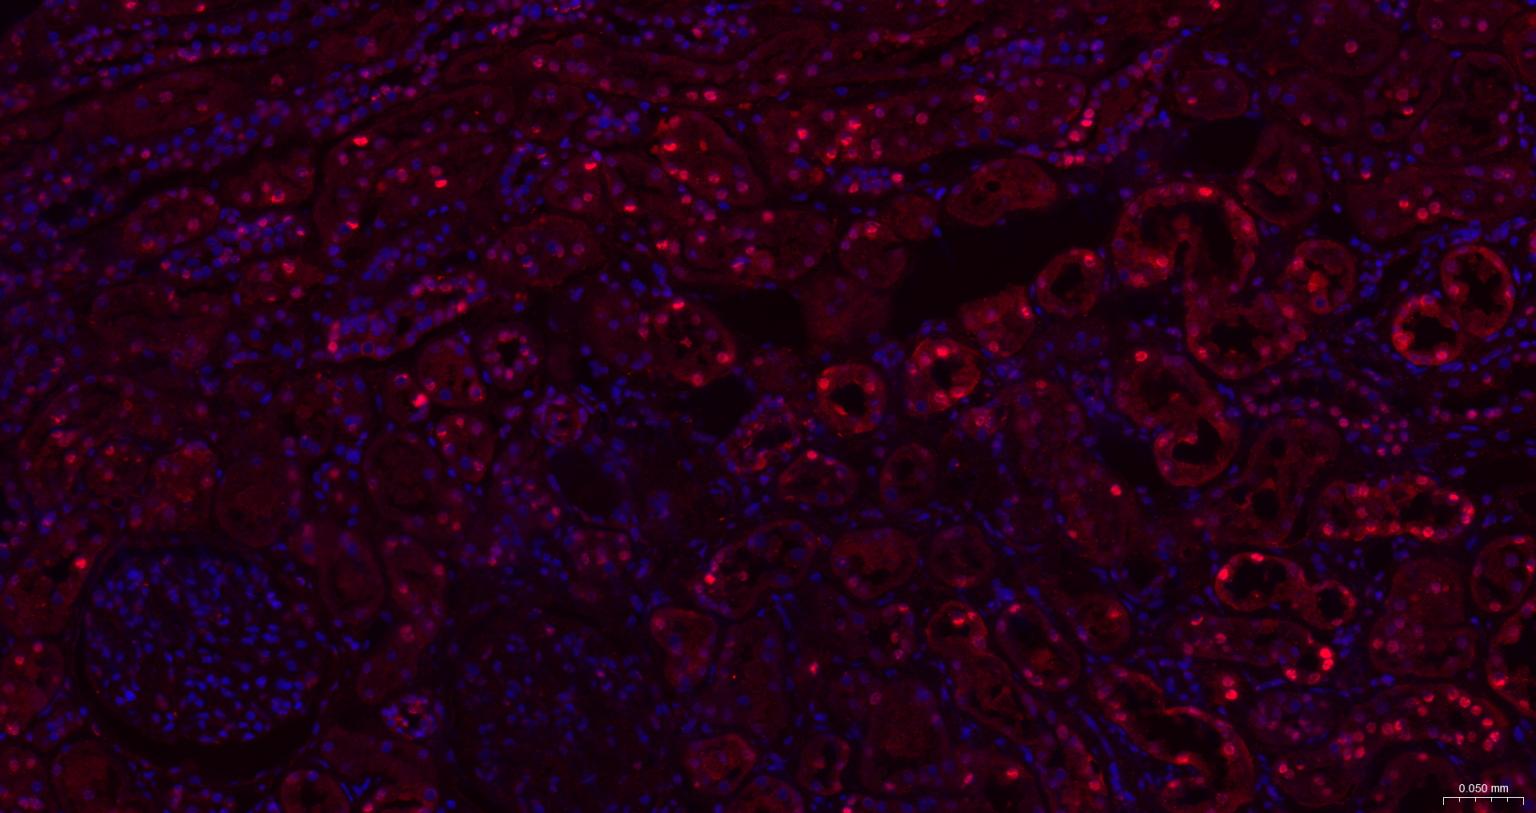

Paraformaldehyde-fixed, paraffin embedded Human Colon Cancer; Antigen retrieval by boiling in sodium citrate buffer (pH6.0) for 15 min; The section was incubated with HDGF Monoclonal Antibody, Unconjugated (bsm-62928R) at 1:200 overnight at 4°C. Followed by conjugated Goat Anti-Rabbit IgG antibody (Red, bs-0295G-BF594), DAPI (blue, C02-04002) was used to stain the cell nuclei.

Paraformaldehyde-fixed, paraffin embedded Mouse Kidney; Antigen retrieval by boiling in sodium citrate buffer (pH6.0) for 15 min; The section was incubated with HDGF Monoclonal Antibody, Unconjugated (bsm-62928R) at 1:200 overnight at 4°C. Followed by conjugated Goat Anti-Rabbit IgG antibody (Red, bs-0295G-BF594), DAPI (blue, C02-04002) was used to stain the cell nuclei.